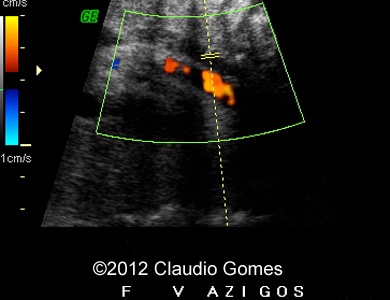

Image 2: Routine transverse view of the abdomen and thorax showing a vessel posterior and to the right of the aorta (Azygos vein).

Fig3

Images 4, 5: 26 weeks-Persistent right umbilical vein and again a vessel posterior and to the right of the aorta (Azygos vein).

Images 8-11: Persistent right umbilical vein and Inferior vena cava interruption with continuity of the flow via Azygos vein on grayscale and color Doppler

Fig8

Fig9

Fig10

Fig11